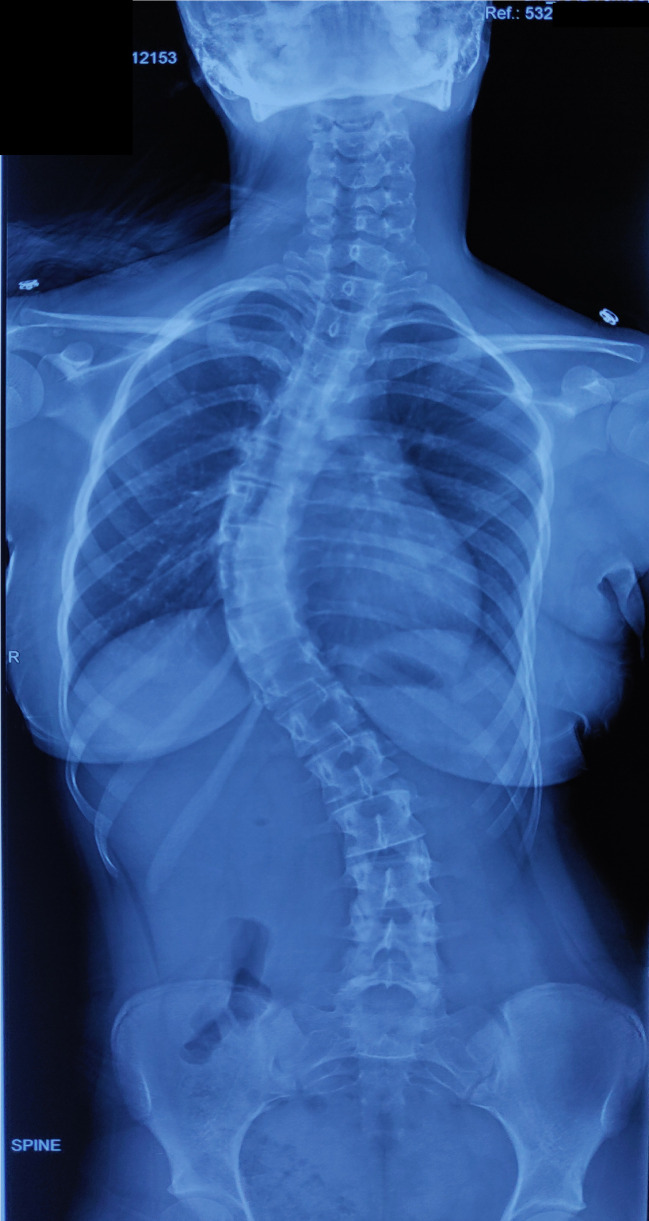

Figure 2.

Posteroanterior and lateral whole spine x-ray of 18-year-old female patient with 11 thoracic vertebrae.